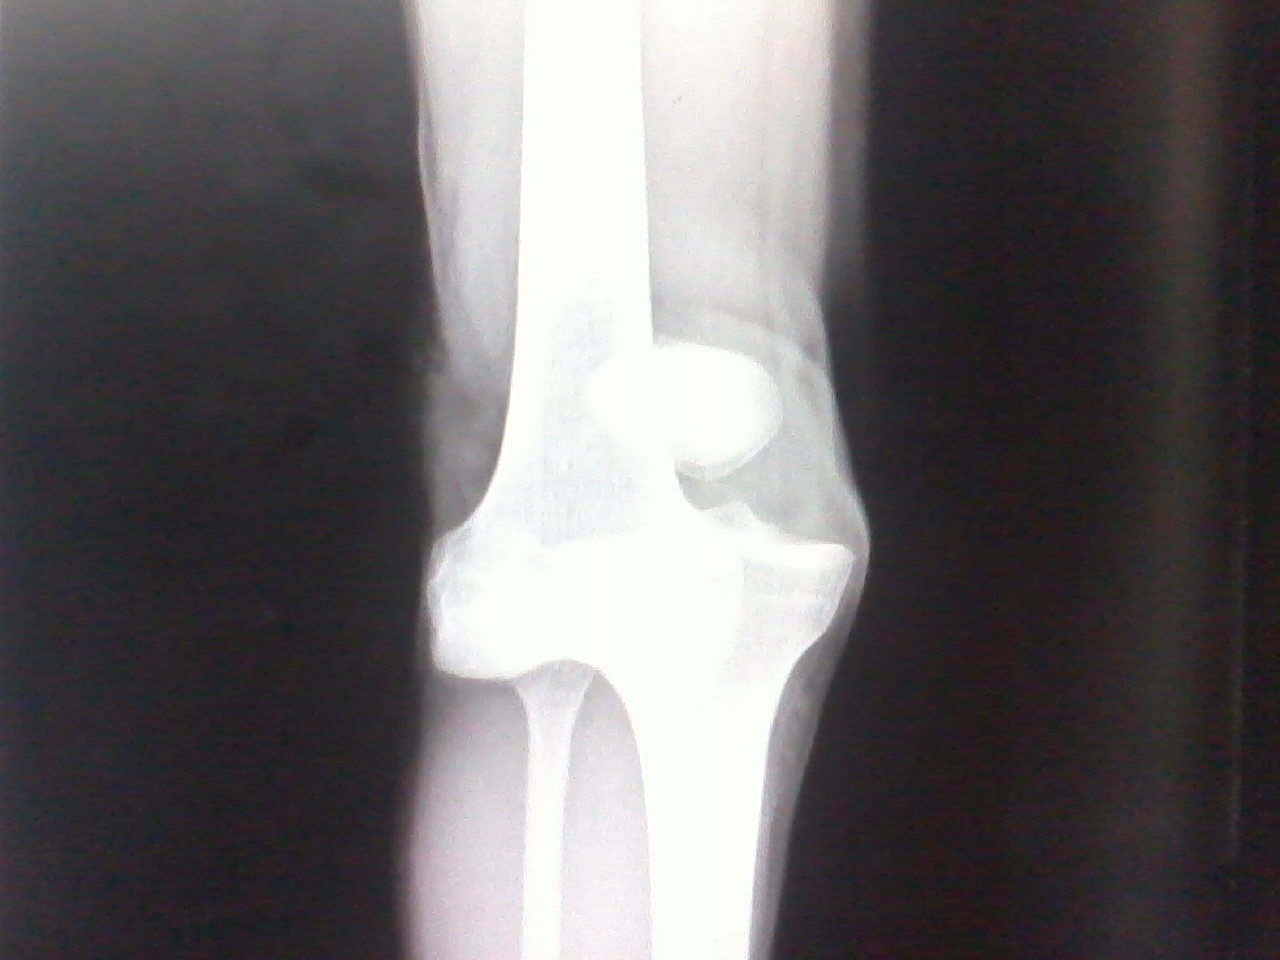

Doctors commonly use imaging scans such as X-ray, MRI, and CT scans to produce an image of your bones and cartilage. This helps them rule out other causes of your symptoms, such as bone spurs.

X-rays. Because a torn meniscus is made of cartilage, it won’t show up on X-rays. But X-rays can help rule out other problems with the knee that cause similar symptoms.

- X-rays to see if the kneecap is out of place and check for broken bones.